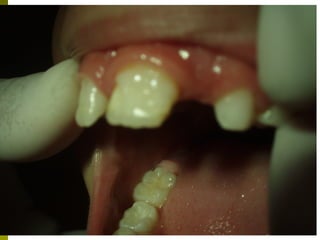

Ανωμαλίες διάπλασης της αδαμαντίνης

 Παθογεvνετικά διακρίνονται δύο μορφές

υποπλασία – μια ποσοτική ανωμαλία

της αδαμαντίνης, εντοπισμένη ή

γενικευμένη μείωση του πάχους που

οφείλεται σε διαταραχές στην εκκριτική

φάση

 Υπενασβεστίωση – διαταραχές κατά το

στάδιο της ενασβεστίωσης, έτσι τμήματα

της αδαμαντίνης αποσπώνται γρήγορα

Υπενασβεστίωση γομφίων και τομέων

 Επιπολασμός 4 - 25% ανάλογα με τον

πληθυσμό που εξετάζεται

 Ο αριθμός των δοντιών ποικίλει από ένα

έως τέσσερα

 Ο βαθμός προσβολής ποικίλει από ελαφρώς

έως βαριά